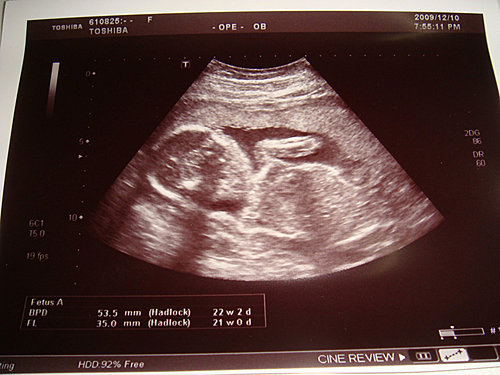

今天和朋友去古典玫瑰園吃午餐,不曉得是我吃的東西造成的,還是懷孕的胎火,到了五點多,我全身起了疹子,而且其癢無比,忍耐到六點半,去婦產科報到,醫生就開了擦和吃的藥給我,之後又用超音波照一下bb,他又長大了許多,不過醫生還是交待我要多躺,因為現在bb的位置還是太低,姿勢是橫躺,怕我會前置胎盤,所以我真的要乖乖給他躺躺躺了。

BPD→頭的橫徑,53.5mm22w2d

FL →大腿骨的長度,35.0mm21w0d